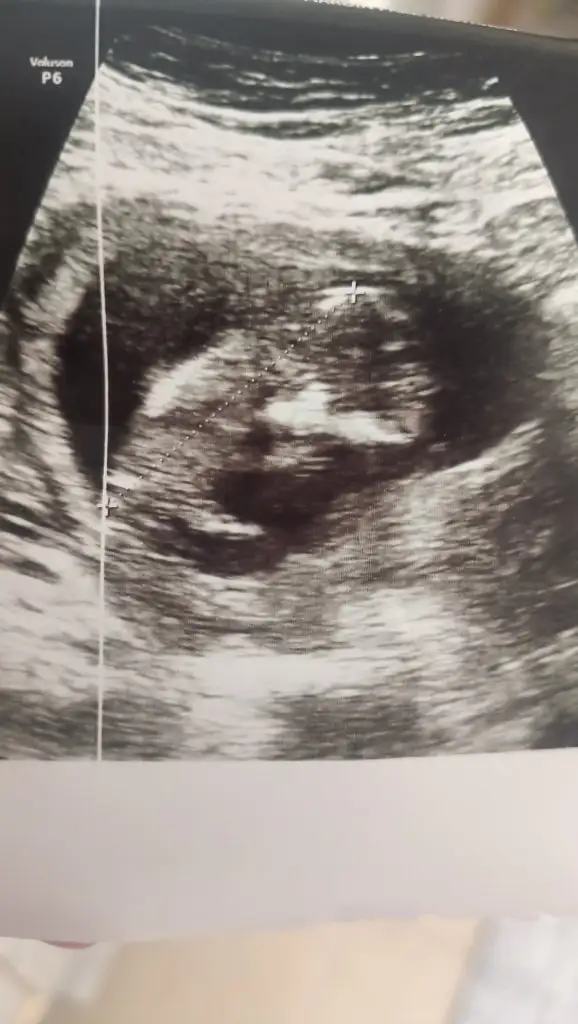

İnşallah canım önemli olan o zaten ama yinede insan coo merak ediyor anlıyorum sizleriAhahaha ters köşe yapmış desene valla her ikisine de okeyim yeterki sağ salim kucağıma alım bu sefer![]()